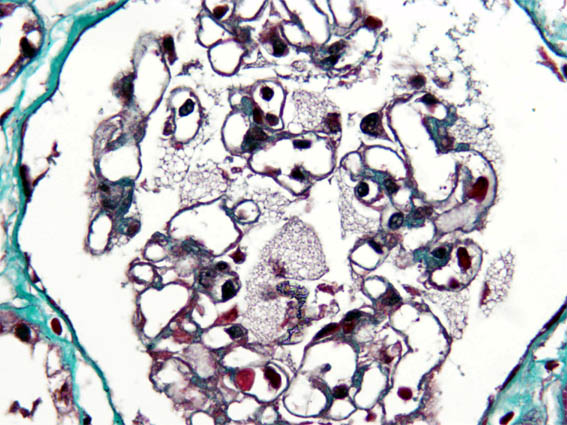

Clinical information

See the images of the renal biopsy.

Figure 4. Masson's trichrome stain, X400.